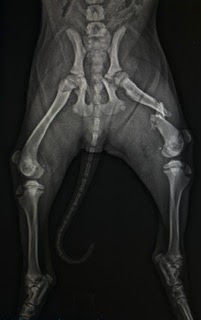

According to the veterinarian’s report, the injuries were not just simple breaks — they were multiple, complex fractures involving both the hip socket (acetabulum) and the thigh bone (femur).

Buddy’s femur was “comminuted and displaced,” meaning it was shattered into multiple sharp fragments and pushed out of alignment. Each broken edge of bone would have caused excruciating pain, cutting through surrounding muscle and tissue.

X-rays revealed that even the metaphysis, a critical area near the growth region of the bone, was broken — an especially painful and serious location. The hip fracture made every movement of his leg unbearable, leaving him unable to stand, walk, or even shift position without agony.

Surgeons had to remove bone shards and reconstruct his leg piece by piece using metal plates, screws, and wire to hold the splintered bones together.

A 12-hole locking plate with screws was implanted to re-attach and secure the broken femoral pieces. This level of surgical repair is typically reserved for the most severe trauma cases.